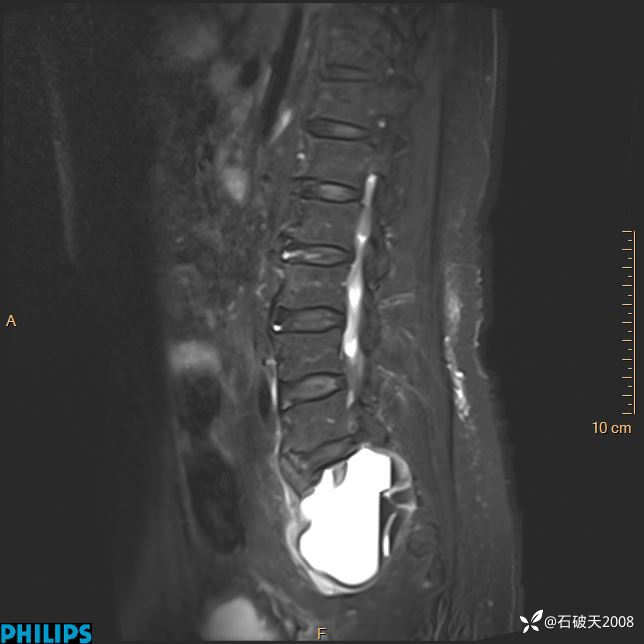

2023年3月份MRI影像

T2矢状位

T2矢状位压脂